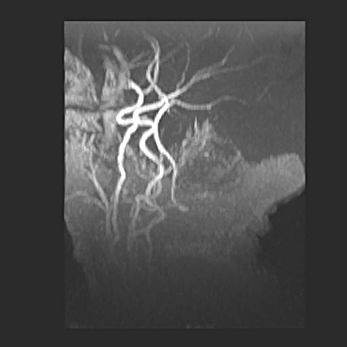

Сообщающаяся гидроцефалия. Кистозная энцефаломаляция головного мозга.

Возраст: 3 месяца 4 дня

Вес: 3100 г

Пол: женский

Окружность головы: 34 см

Срок гестации: 31 неделя

Кистозная энцефаломаляция головного мозга - одна из форм поражения головного мозга в детском возрасте. Характеризуется возникновением множественных и распространённых кист в коре, белом веществе и подкорковых образованиях головного мозга у плодов, новорождённых и детей раннего возраста. Развитие кистозной энцефаломаляции связано с внутриутробной асфиксией и гипотонией, родовой травмой, тромбозом синусов, пороками развития сосудов, инфекциями, сепсисом и другими причинами. Наиболее значимые инфекционные агенты: вирусы простого герпеса, цитомегалии, краснухи, токсоплазмы, энтеробактерии, золотистый стафилококк и другие.